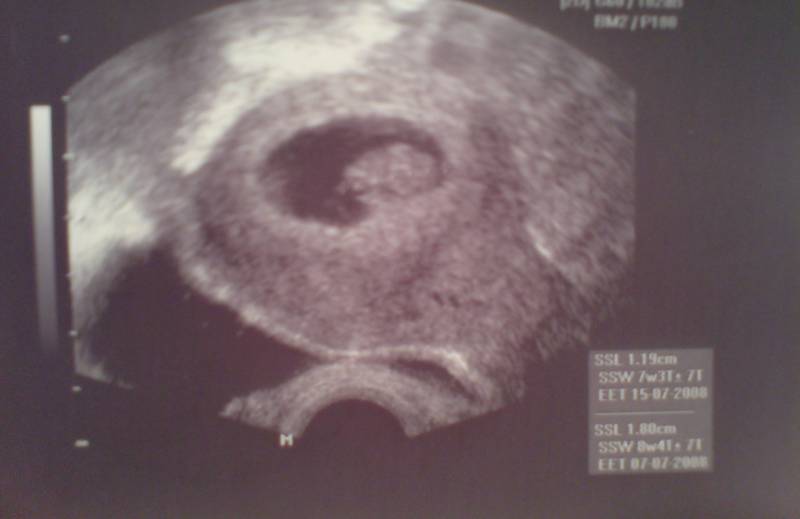

8+0 9. SSW Datum 19.05.2008 9. SSW